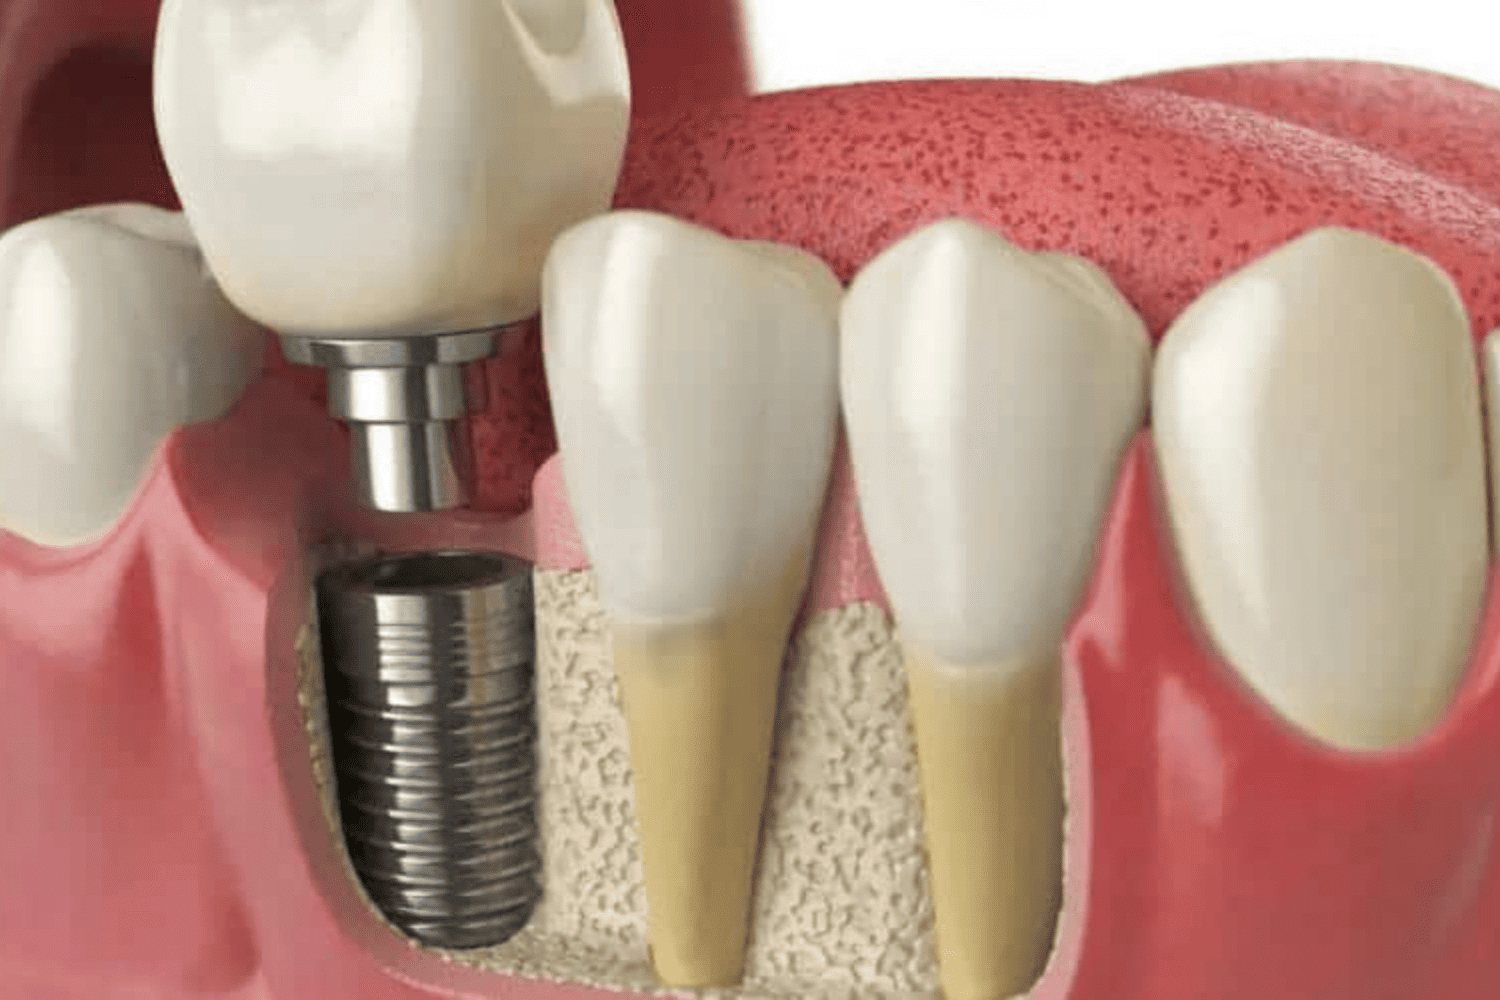

READ MOREDental Implants in Jaipur Services Crowns Bridges Dentures...